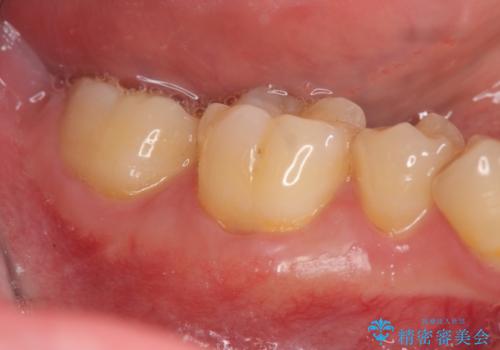

![[嘔吐反射がひどく義歯がつけられない] 臼歯部インプラント補綴 の症例 治療前](https://seimitsushinbi.jp/wp/wp-content/uploads/2020/03/1b03fb94a80967489da3fbc10eca6c8f-500x350.jpg?v=1585390188)